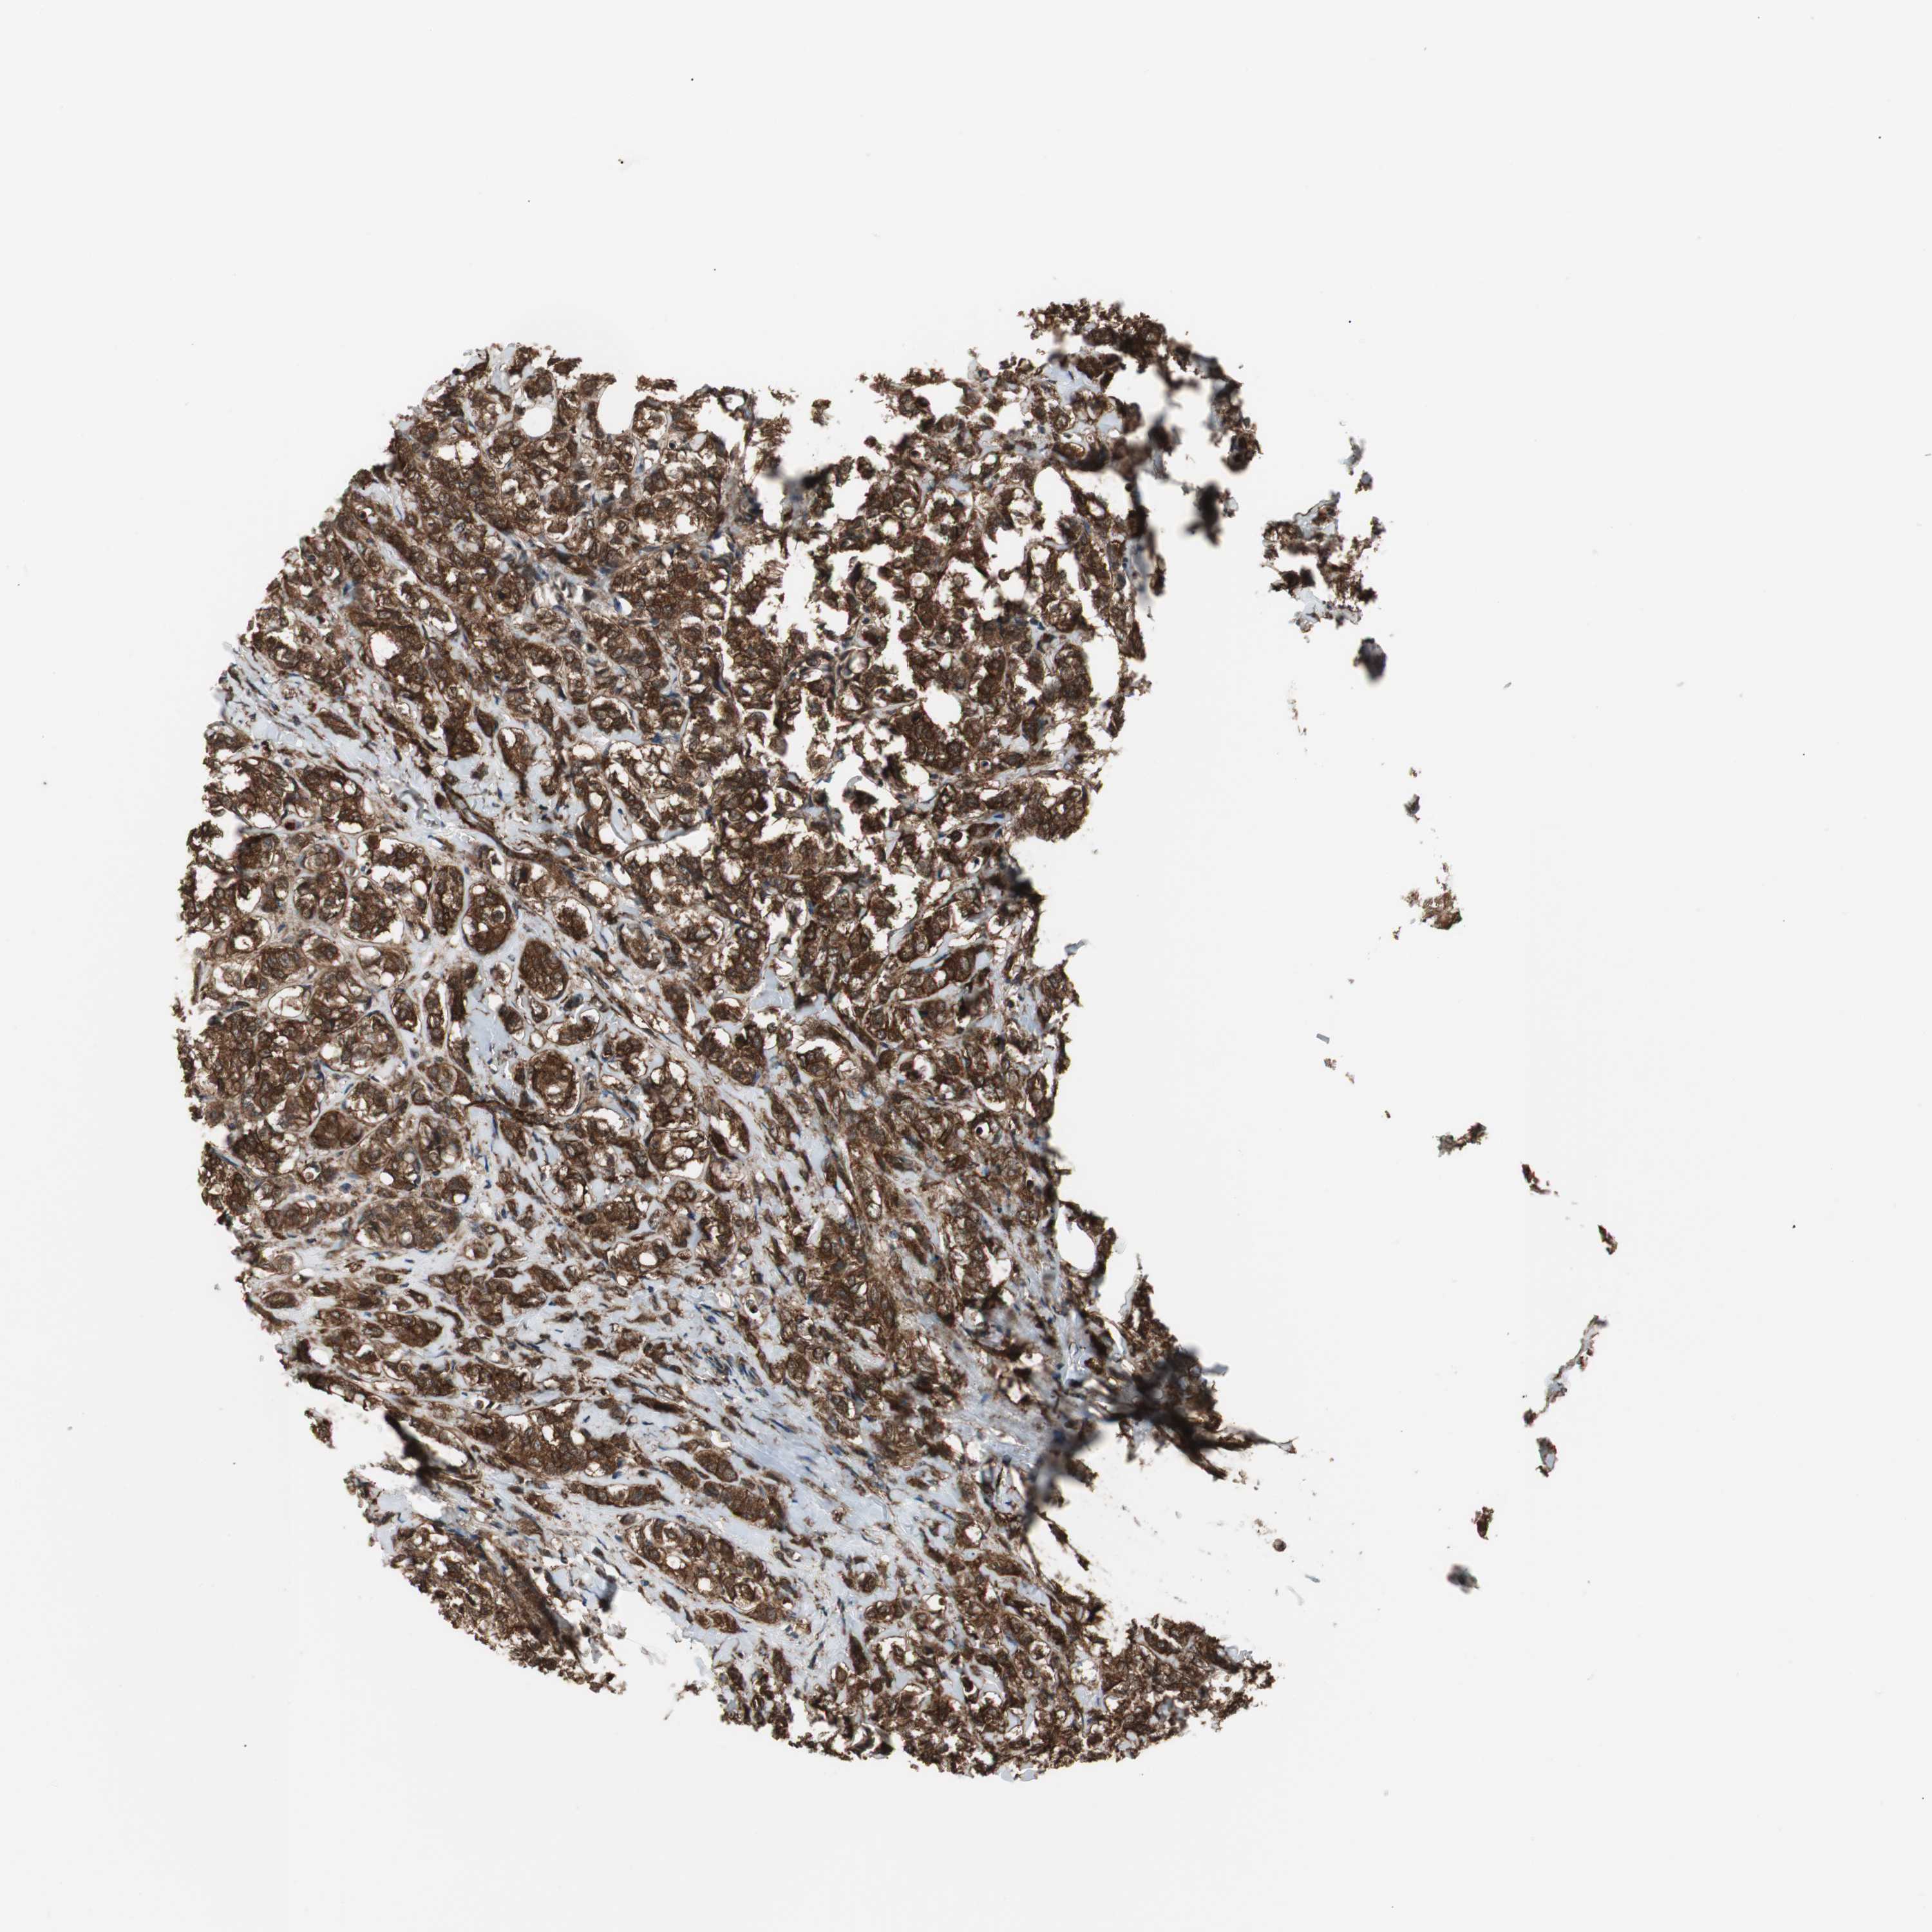

BRCA TCGA BRCA VALIDATION PROTEIN EXPRESSION